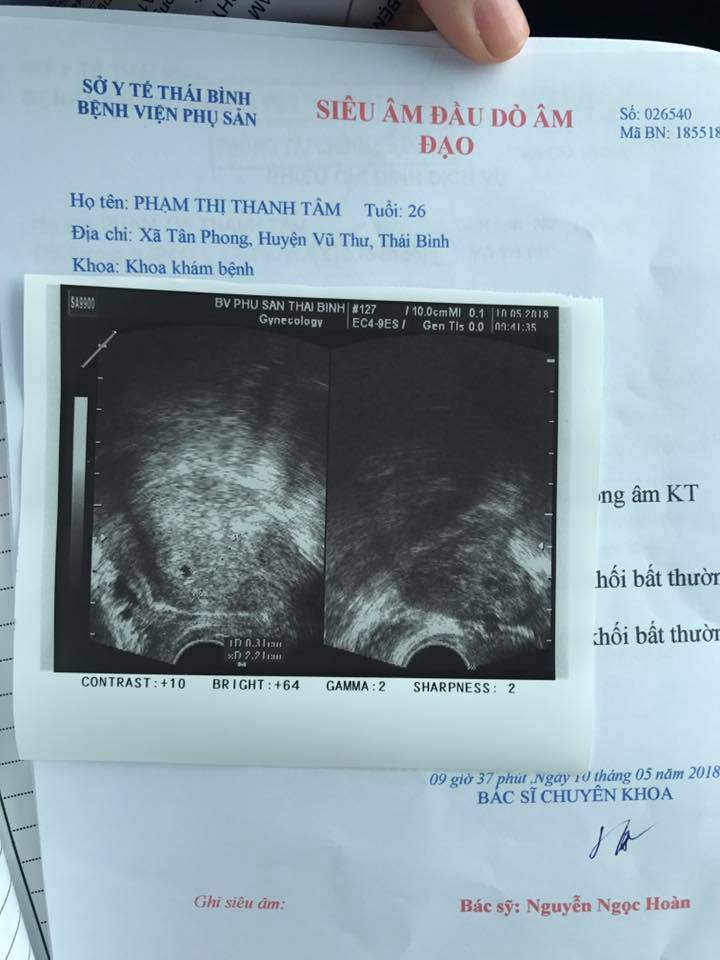

Mẹ nuôi Yến Nhi hiện đã có bầu được khoảng 3 tuần, em bé mới là một phôi thai hơn 3mm và dự sinh đầu năm 2019.